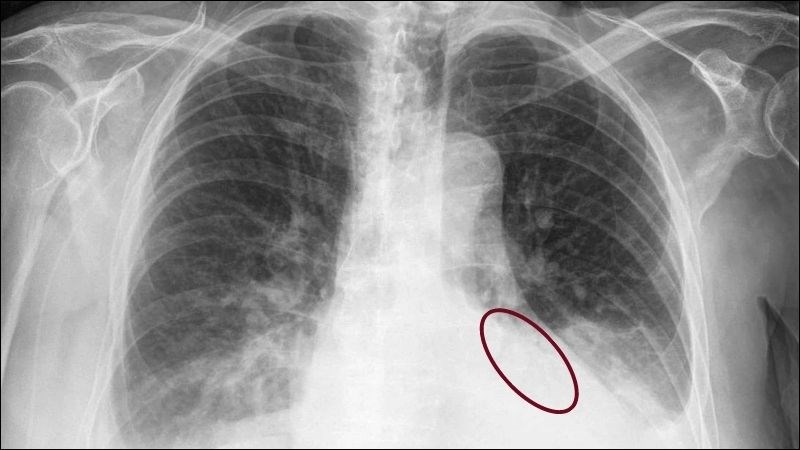

Các xét nghiệm và chẩn đoán hình ảnh thường được sử dụng để chẩn đoán và đánh giá tràn dịch màng phổi bao gồm:[3]

- X-quang ngực: Đây là phương pháp chẩn đoán hình ảnh thường dùng nhất để kiểm tra sự tồn tại của dịch trong khoang màng phổi.

Các xét nghiệm hình ảnh lồng ngực rất có ý nghĩa trong chẩn đoán tràn dịch màng phổi